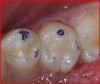

Fig 7. Upon removal of the failed amalgam restoration, remnants of the previously placed and now broken-down calcium-hydroxide liner were observed, along with recurrent caries and stained margins in the left lobe from microleakage.

Figure 7

Fig 8. The calcium-hydroxide liner was removed, as was the underlying carious dentin. The microleakage stain on the left lobe was removed after photographing.

Figure 8